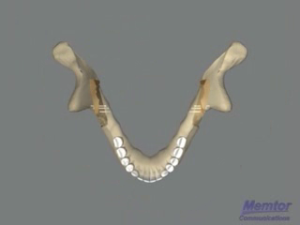

Recul mandibulaire - Vue osseuse 1